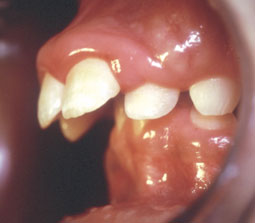

Meryème M âgée de 9 ans lors des premiers examens complémentaires (radiographies, modèles et photographies). Cette jeune patiente présente une classe II 1 Hyperdivergent, supraclusie et encombrement incisif inférieur important en denture mixte.

Photographies intrabuccales

Avant traitement (Fig. 4-9) |